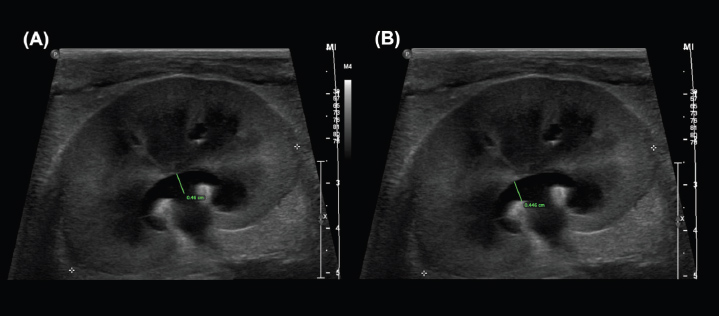

Discussion

The greatest overall interobserver agreement was achieved by standardized measurements between the renal crest and proximal ureter in the dorsal (DCU) and transverse (TCU) planes (Figs. 2a and b), even though anatomical definitions of the ‟ureteropelvic junction” are lacking in the veterinary and human medical literature (Stringer and Yassaie, 2013). One review of literature examining normal human kidneys concluded that a discrete pyeloureteral junction might not be present, and that in most individuals there might be a gradual zone of transition between the pelvis and ureter. Similar studies are lacking in the veterinary literature. While the unipyramidal morphology of the feline kidney differs from that of the multipyramidal kidney in humans, the embryological development is comparable (Hyttel et al., 2010), and a similar ‟pyeloureteral region” might also be expected in these patients. The ambiguous definition of the pyeloureteral junction might have less impact on interobserver agreement in specific images, however, if the angle of insonation is not perfectly centered and parallel to the long-axis of the proximal ureter. In this scenario, the medial cortical parenchyma or adjacent hilar fat may appear as a discrete, faint echo at the medial aspect of the collecting system due to slice thickness artifact. These echoes could provide a ‟pseudo-margin” for calliper placement, which could increase interobserver agreement. We attempted to minimize the effects of these phenomena by providing clear instructions and allowing the observers to reject images that they considered inappropriate for interpretation in a clinical setting. Our results, therefore, likely reflect the standard that would be encountered during retrospective measurement of still images in clinical practice. Furthermore, if a standardized measurement can be performed reliably and found to correlate with or differentiate between clinical entities, it has value as a diagnostic tool. In these circumstances, whether the region measured represents the precise anatomical boundaries of the renal pelvis is not as important as the reliability with which the measurement can be repeated between observers.

Fig. 2. Examples of the DCU (A) and TCU (B) measurement methods, which had the highest interobserver agreement of all methods examined in this study.